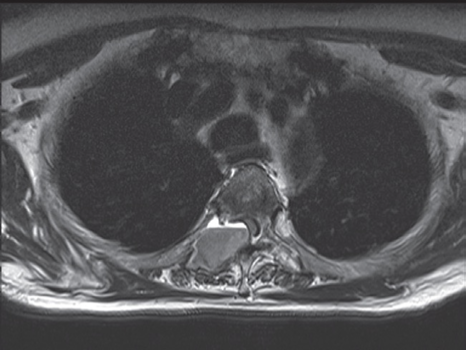

Axial T1-weighted image

showing a breast cancer metastasis

arising from the right pedicle and causing extradural compression of the cord.